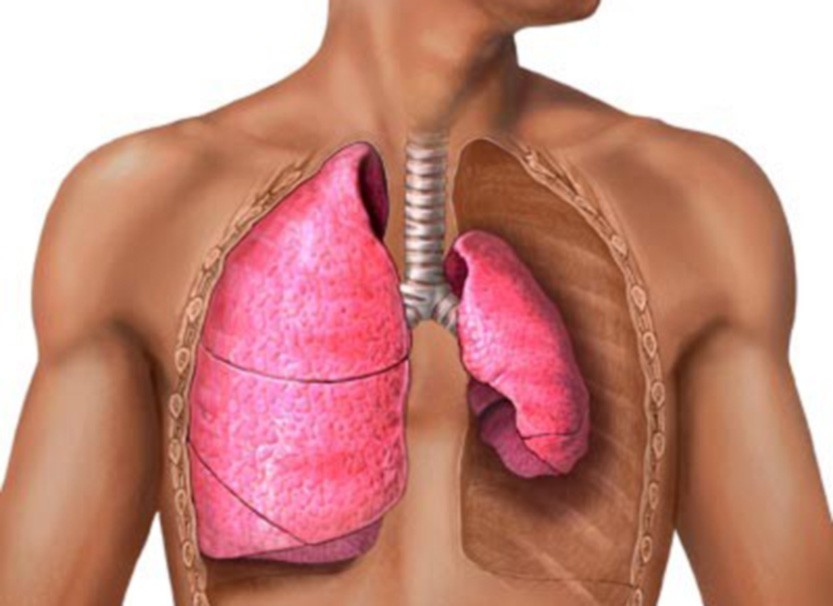

Симптомы и причины скопления воды в легких